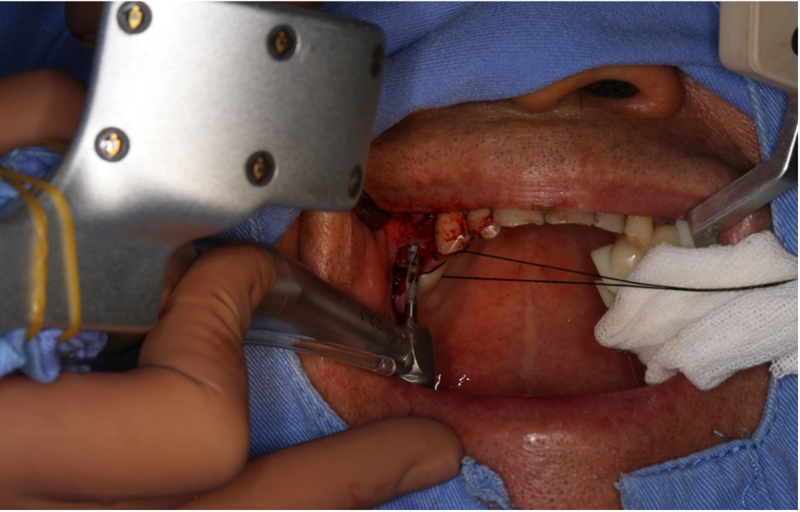

®按照術前方案進行備洞及植體植入

®按照術前方案進行備洞及植體植入,醫(yī)生可以通過屏幕軟件引導對手術中植入點、角度、深度實時追蹤

®對植體深度及方向進行確認

®完成3顆植體的植入,植體位點如術前方案設計,均在同軸線。

®進行縫合

®該患者需連續(xù)種植三顆植體,手術難度高。需保證相鄰植體位置關系符合種植要求。徒手種植難以保證其位置一致性。

®如果翻瓣后發(fā)現(xiàn)患者實際情況與種植設計不符,迪凱爾易植美軟件能及時調(diào)整手術方案。主刀醫(yī)生使用導航軟件無需借助額外輔助工具,對種植過程中術區(qū)散熱以及開口度和視野都無影響。